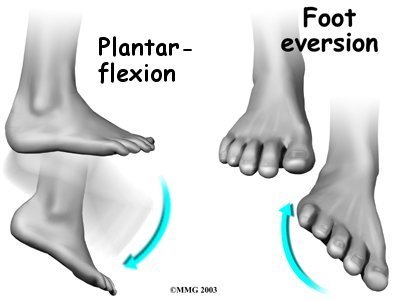

The tendons of the peroneal muscles pass together through a groove behind the lateral malleolus. The tendons are kept within the groove by a sheath that forms a tunnel around the tendons. The surface of this sheath is reinforced by a band of ligament called a retinaculum. Contracting the peroneals makes the tendons glide in the groove like a pulley. This pulley action points the foot downward (plantarflexion) and outward (eversion).